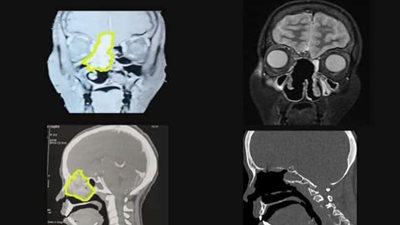

نجح فريق جراحات مناظير قاع الجمجمة في استئصال ورم دموي نادر بالأنف يمتد إلى داخل المخ بالتعاون بين قسم جراحة